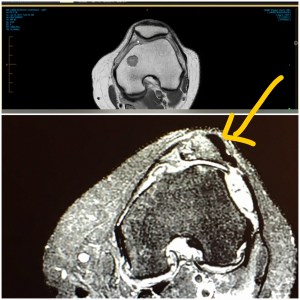

The results from the MRI showed a torn meniscus, some bursitis and most debilitating, a severely misaligned patella.

My patella is noted to be on the verge of dislocation at all times. My formerly conservative doctor went from telling me to wait a few years for my inevitable surgery to warning me that if I wait too long, surgery won’t even be an option I’ll let him tell it: